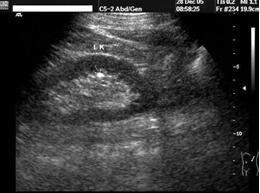

好多市民一提起肾结石这个病可是谈虎色变,觉得会疼的死去活来的,从而忧心忡忡,下面呢我给大家看一张彩超下的肾结石究竟长什么样子

看到了吗?肾结石是一些晶体物质和有机基质在肾脏的异常聚积所致,为泌尿系统的常见病、多发病,男性发病多于女性,多发生于青壮年,左右侧的发病率无明显差异。40%~75%的肾结石患者有不同程度的腰痛。结石较大,移动度很小,表现为腰部酸胀不适,或在身体活动增加时有隐痛或钝痛。较小结石引发的绞痛,常骤然发生腰腹部刀割样剧烈疼痛,呈阵发性。